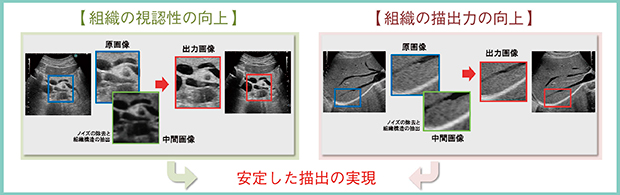

Carving Imagingでは,組織構造特性を空間的に解析して,(1) 高輝度の飽和を抑えながら輝度変化のある箇所をエッジとしてシャープに強調,(2) 空間的に構造と判断した場合には結像処理を実施,(3) 低輝度で輝度変化が少ない部分(血管や胆嚢の内腔など)を「抜け」としてノイズ除去,という処理を行う。これらをデノイズした画像に適用することで,ノイズレスで組織結像力が高い画像を実現し,組織構造の視認性と描出力の向上により患者および検者依存性の少ない安定した描出が可能となった。つまり,Carving Imagingでは,低周波による深部の乱れを低減し,高周波のような画質が得られるということであり,従来の画像では不明瞭であった病変構造物を,誰でも簡単に描出可能となる(図1)。eFocusingによる元画像の画質向上と相まって,さらなる画質の向上と効率化(診断のしやすさ)に貢献している。

図1 Carving Imagingの概要